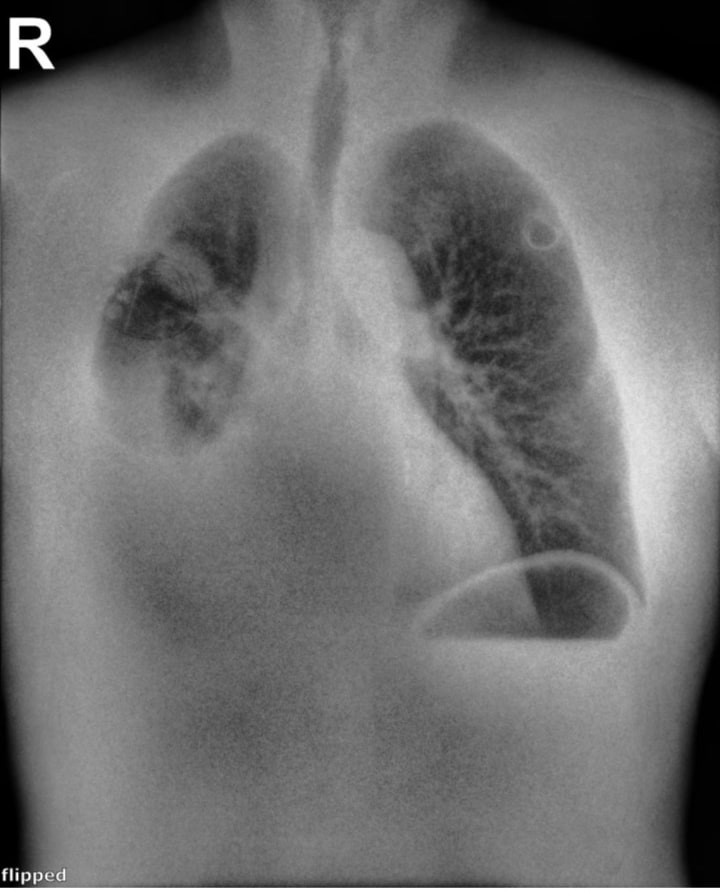

This 26-year-old male presented to the ER at 3am, with difficulty breathing and chest pain. The Reveal 35C Spectral DR detector was used to generate all 3 images. A left apical pneumothorax can be visualized, and is best seen in the Soft Tissue image.